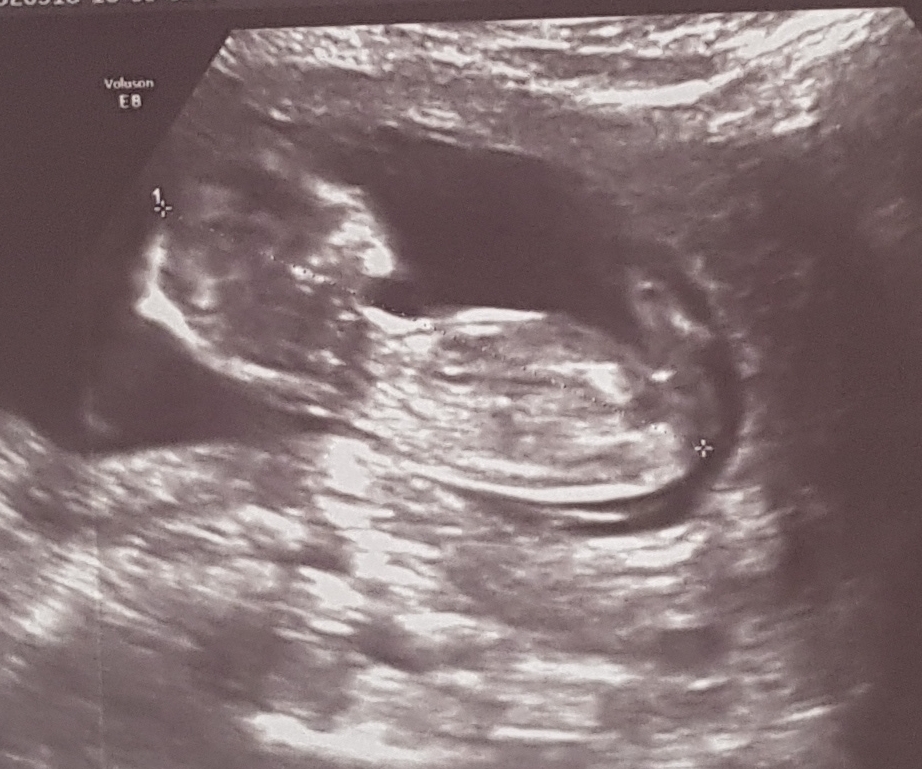

H Haleee Yeni Üye Üye 12 Mart 2018 #69 Svgnnn' Alıntı: canım ense kalınlııgını ölçen bayan radyolog bana kız gibi dedi ultraso. Fotosu da bu seninkini atarmısın Genişletmek için tıkla ... Maasallah Allah bagislasin Benimki boyle🙂 12+3 haftalikti burda

Svgnnn' Alıntı: canım ense kalınlııgını ölçen bayan radyolog bana kız gibi dedi ultraso. Fotosu da bu seninkini atarmısın Genişletmek için tıkla ... Maasallah Allah bagislasin Benimki boyle🙂 12+3 haftalikti burda